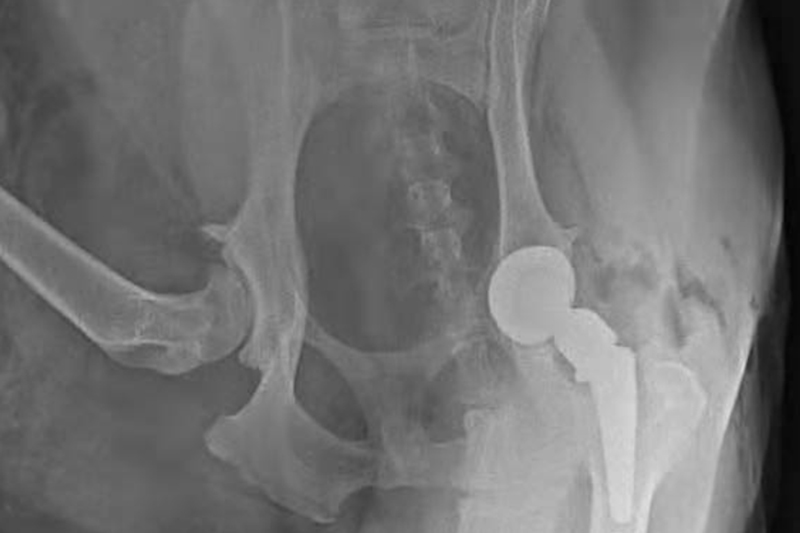

How should pet owners decide to undergo hip replacement surgery?

As the owner of a dog, facing the major medical decision of hip replacement surgery, it is necessary to comprehensively evaluate from multiple dimensions such as hospital qualifications, doctor exp...